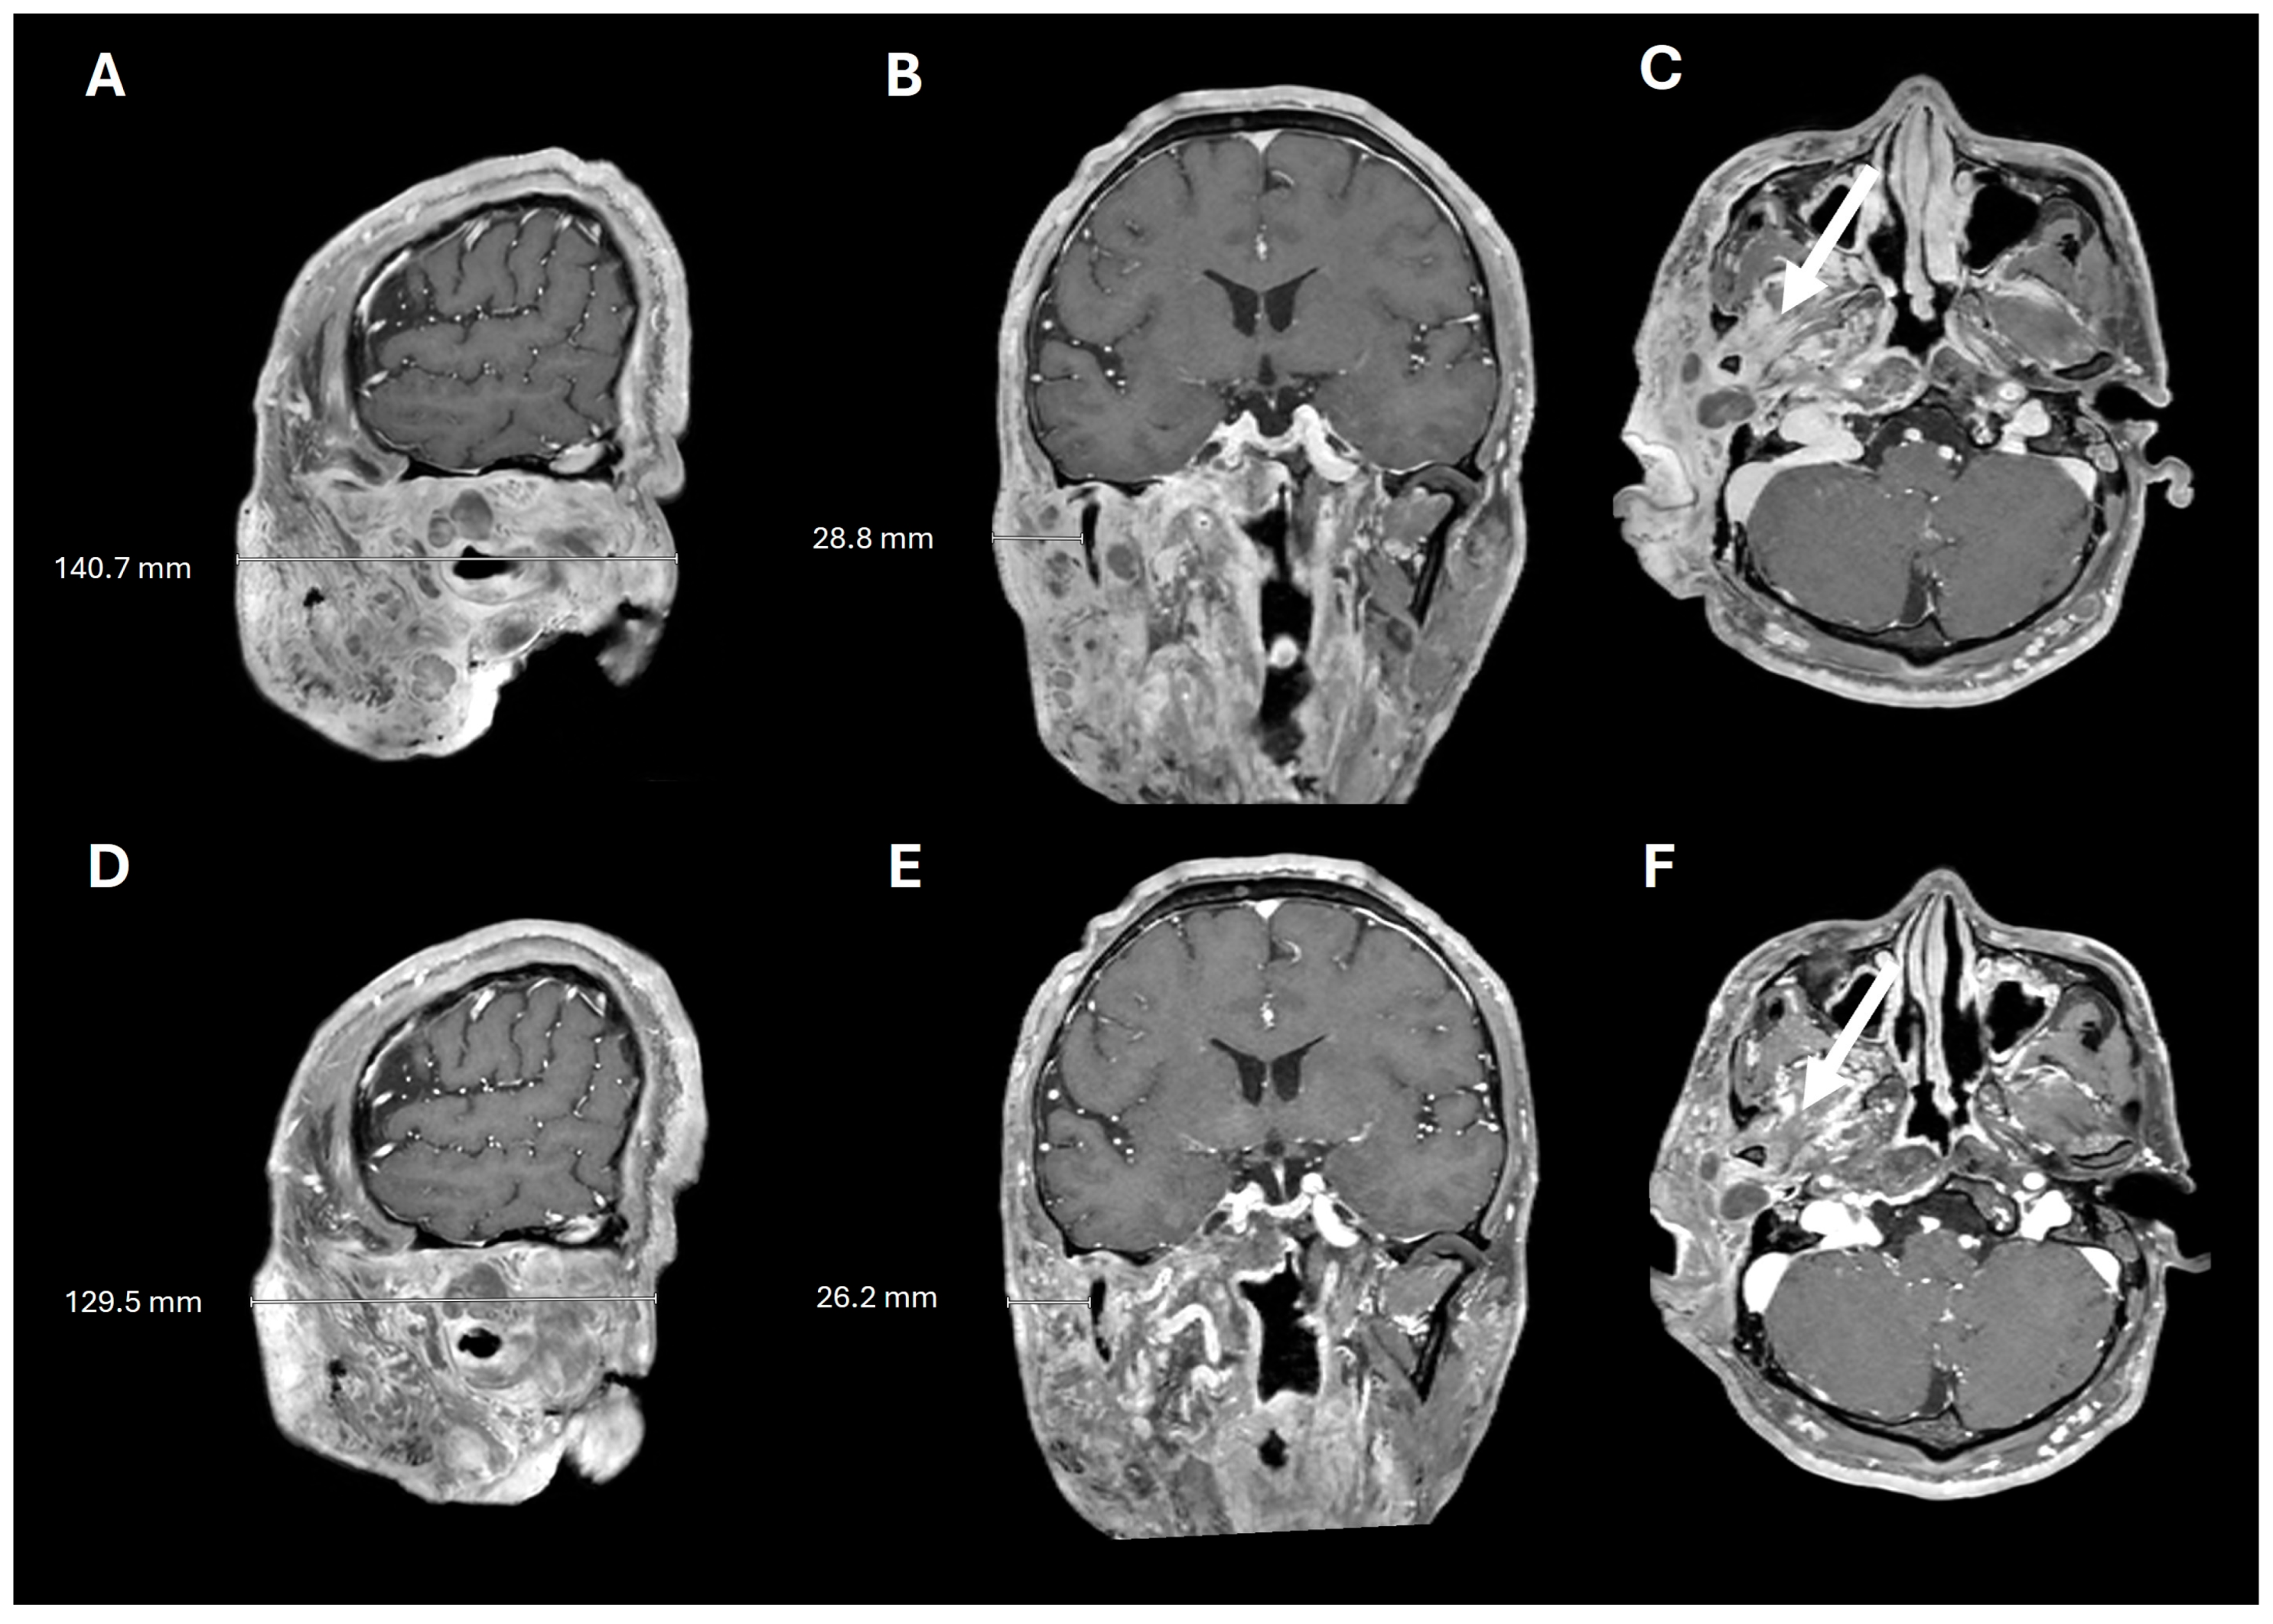

Figure 4.

Pre- and post-selumetinib brain MRI. T1+contrast imaging before (A–C) and after (D–F) 7 months of selumetinib, showing decreased tumor burden and decreased tumor infiltration into the masticator space (arrows).

A 38-year-old man with genetically confirmed NF1 and a large conglomerate R facial PN, with status post debulking at age 8, presented to our institution for further management of his disfiguring PN. His family history was positive for NF1 in his mother and daughter. Genetic testing revealed a heterozygous pathogenic truncating variant in exon 38 of NF1: c.5438C>A and p.Sesr1813Ter. No reportable variants were found in SPRED1. Neurological examination showed a large right facial mass (Figure 1A), >6 café au lait macules—all >15 mm in size, axillary freckling, and numerous cutaneous neurofibromas. A brain MRI demonstrated a right predominantly facial PN (Figure 2A–C). Following posterior auricular tumor debulking, a brain MRI showed an interval reduction in the tumor size posterior to his ear (Figure 2D–F). Pathological examination showed positive S100, SOX-10, and CD34, and negative SMA, consistent with neurofibroma (Figure 3). Ki-67 was less than 1%. Molecular analysis identified a pathogenic variant (NM_000267.3: c.5438C>A, p.Ser1813Ter) in the heterozygous state in NF1. At the time of diagnosis, there were no FDA-approved agents for adult NF1 PNs. On the basis of the higher reported ORR in selumetinib compared to mirdametinib, selumetinib was the targeted agent selected for our patient. However, no head-to-head clinical trials have directly compared mirametinib and selumetinib. He was administered 25 mg/m2 (40 mg BID) selumetinib, which was complicated by a facial acneiform rash and asymptomatic elevated Grade 3 CPK after 1 month. His rash resolved with topical adapalene 0.1%/benzoyl peroxide 2.5% gel, and his CPK improved to Grade 1 with a dose reduction in selumetinib to 35 mg BID. At 7-month follow-up, a reduction in tumor burden was noted clinically (Figure 1A–C), with a corresponding reduction in tumor volume radiographically (Figure 4A–F). On his brain MRI, the pre-selumetinib tumor volume was 284.65 cm3 and the post-selumetinib tumor volume was 236.92 cm3, showing a 16.77% reduction in tumor volume. Given the infiltrative nature of the tumor, volume was calculated using an ellipsoid volume formula of 0.5 × length × width × height. At time of publication, he remains on selumetinib and endorses improvement in quality of life (QoL).